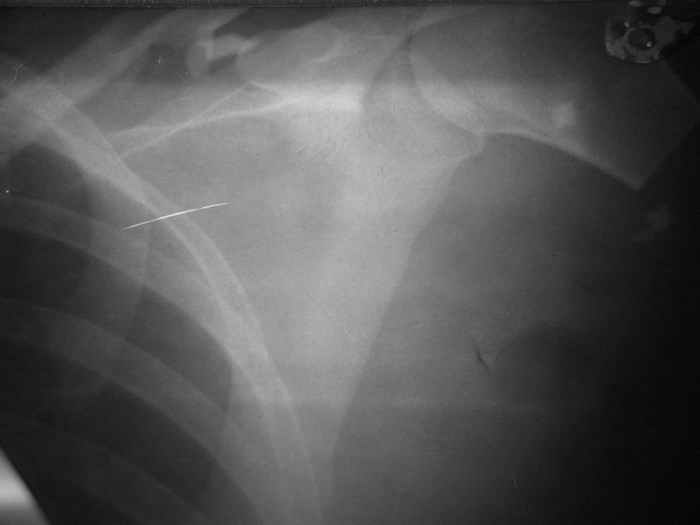

У больной З. 26 лет, пострадавшей в результате ДТП (08.08.05.), имеется травматическая ампутация левой верхней конечности на уровне проксимального отдела плечевой кости, закрытый оскольчатый перелом левой ключицы со смещением отломков.В ургентном порядке произведено ПХО раны с формированием культи конечности.В настоящее время (22.09.05) культя без признаков воспаления, Выделений не отмечается, заживление полное. Имеются умеренные фантомные боли, особенно во второй половине дня, с ощущением лучезапястного и локтевого суставов.В настоящее время решается вопрос о сроках и методах протезирования конечности.Фоторентгенограмма при поступлении и внешний вид больной на момент выписки прилагаются.